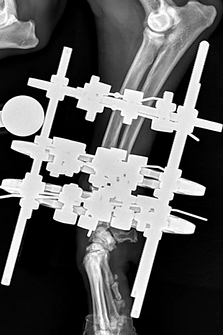

Radiographs (X-rays) are the primary diagnostic tool and may require special views to fully understand the fracture configuration. CT imaging is particularly useful for complex or joint-involving fractures.

Fractures can be treated using a variety of methods, depending on severity, location, and patient factors. Options include:

Surgical repair may use plates and screws, rods or nails, or external fixators. Decisions depend on location, configuration, displacement, soft tissue condition, patient age, and underlying bone health. Prompt treatment is preferred, though life-threatening injuries always take priority. Postoperative care is critical to prevent implant failure and ensure healing.